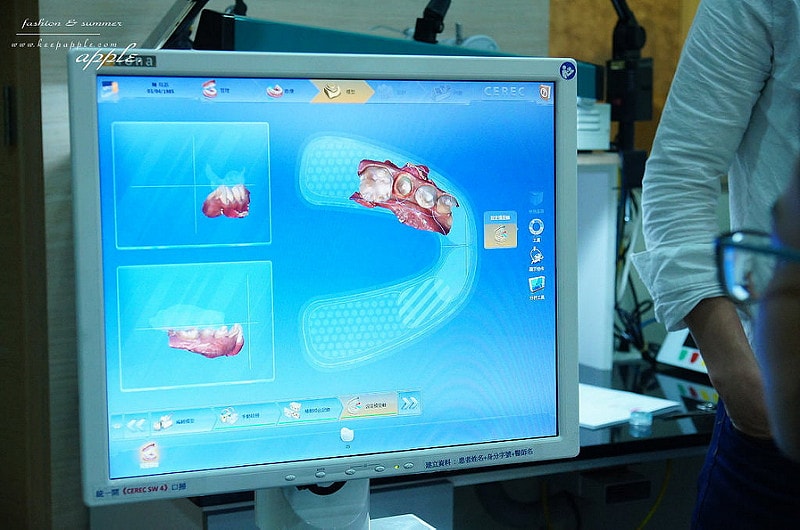

口掃完成之後

資料會傳輸到所有的資料會連動到

>>「3D全瓷冠4軸快速研磨機」上面

當場就可以把假牙研磨出來囉!

接下來就是等待就可以拉

像是掃描跟3D列印的道理一般